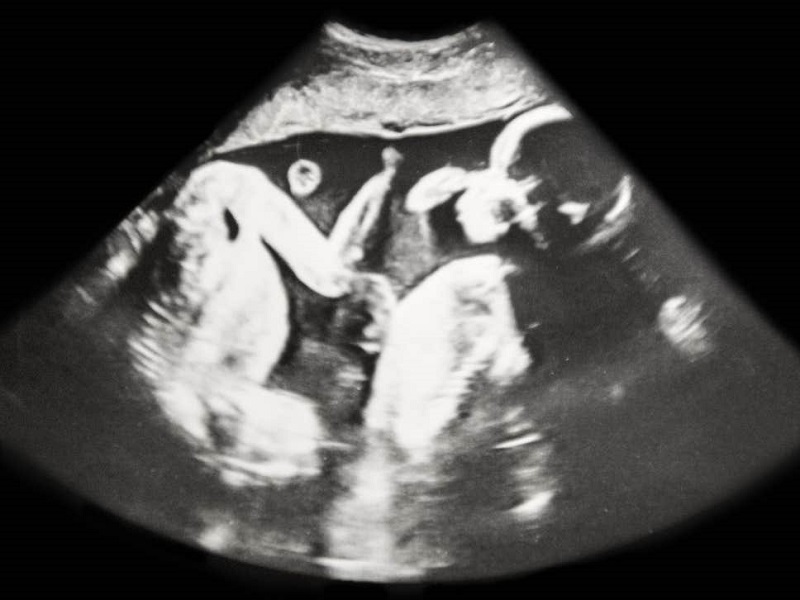

Девојчињата родени со брат близнак може да имаат длабоки промени во животот благодарение на раното изложување на тестостеронот на братот.

Ново истражување покажува дека жените што ја делеле утробата со машки фетус имаат помала веројатност да завршат училиште или универзитет, а имаат и може помалку да заработуваат кога ќе пораснат.

Научниците откриле влијание и врз бројот на деца и стапки на брак, откако ги разгледале податоците за илјадници близнаци родени во Норвешка.

Ефектите се припишуваат на хипотезата за близначки тестостеронски трансфер, во кој хормоните пренесени кај женските од машките имаат трајни ефекти врз нивното однесување.